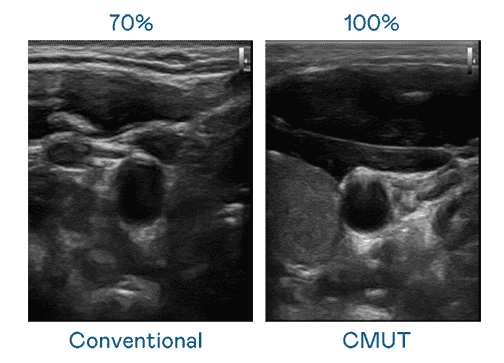

CMUT 技术是一种用电容式微机电元件来产生超音波讯号的技术。。。。与传统 PZT 压电式技术相比,,CMUT 频宽增加 30%,,,,更宽频的超音波讯号让影像解析度大幅提升,,是实现高影像品质医疗超音波扫描、、、促进精准医疗发展的关键技术。。

大频宽带来超清晰影像

超音波影像的解析度高低,,,首先取决于探头能发出的讯号频宽。。。。尊龙z6 CMUT 可提供高清晰的超音波讯号,,提供高频宽、、、、高灵敏度、、、、影像纹理细节更高的超音波影像,,,协助医护人员缩短影像判读时间及利用精准的医疗影像进行诊断。。